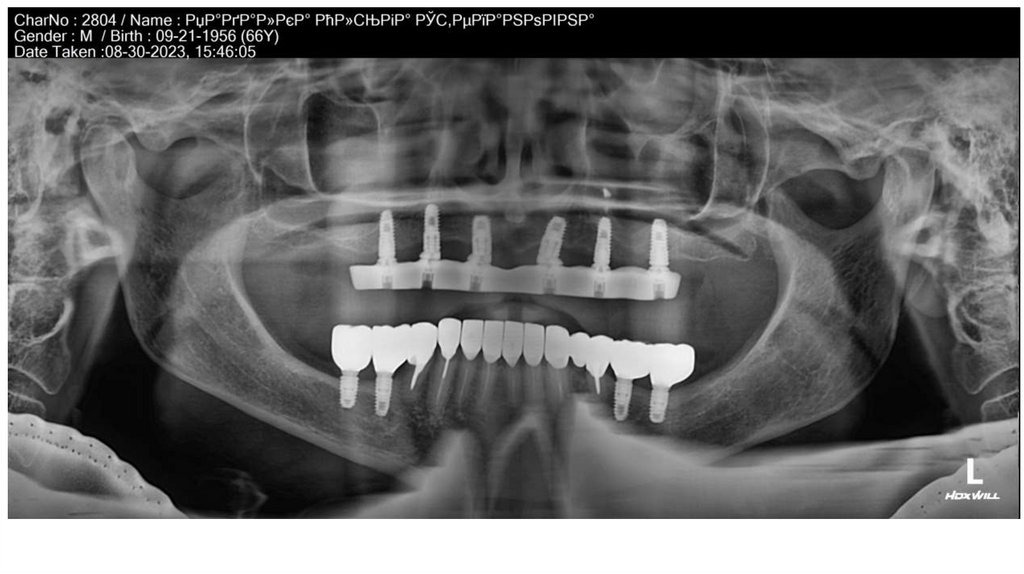

• Можно Мухси и Анатолий посмотрят – эти фото панорамный РгСНИМОК.

• Мне важно ваще мнение такие щели между мультиюнитом и

каркасом должны быть???

• Мне лично кажется – что должно быть все «заподлицо», но

возможно я ошибаюсь.